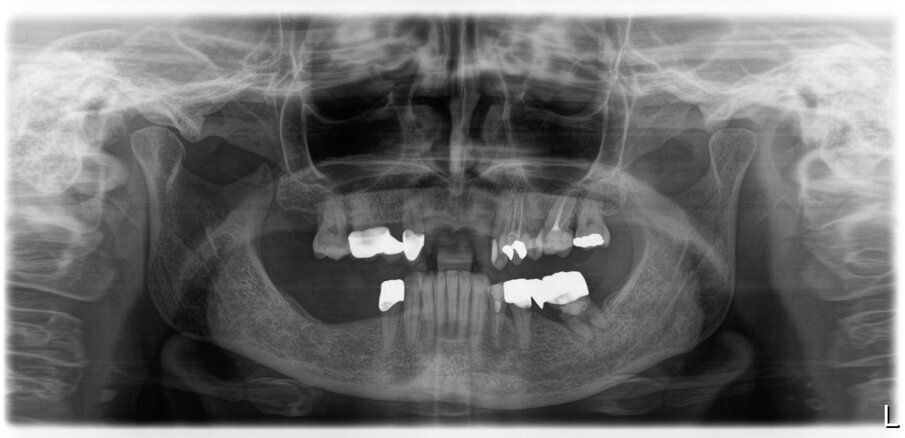

Fig. 50_Radiografia iniziale

Fig. 51_Radiografia a 5 anni dalla consegna del lavoro. Ai follow-up vengono eseguite annualmente delle rx endorali centrate, e alla necessita viene ripetuta un’opt.